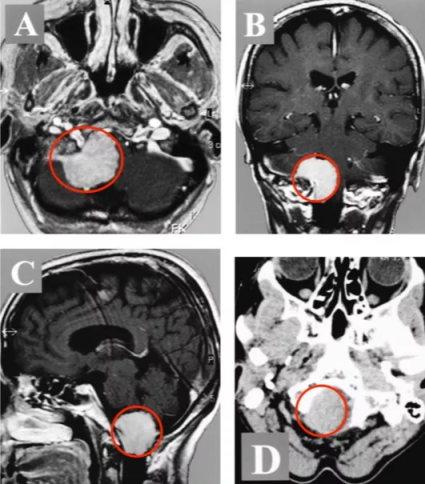

一年后的一个晚上,当Belle出现走路乏力、双脚抬不起来时,一切都变了。她差点摔倒在地,但幸运的是,家人在她摔倒前抓住了她。他们开始意识到这病没那么简单,不查不知道,一查吓一跳,最终发现原来引起上述症状的罪魁祸首不是什么颈椎病,而是在枕骨大孔区区长了一个肿瘤-脑膜瘤(图1)。虽然脑膜瘤90%以上都是良性肿瘤,但其生长的部位实在是太要命了,肿瘤位于下脑干枕骨大孔区,并严重压迫和推挤脑干延髓。加上肿瘤发现的太晚了,体积巨大,导致下脑干在枕骨大孔处被最大限度地压缩,肿瘤占据了90%以上的可用空间。

图1:术前MR显示枕骨大孔区巨大脑膜瘤,压迫脑干、颈髓。